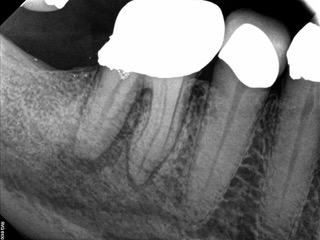

A body of research has emerged in recent years on the management of severe dental pain, exemplified by the diagnosis of an acute apical abscess where drainage cannot be achieved, symptomatic apical periodontitis, or irreversible pulpitis.11 An example of an acute apical abscess is depicted in Figure 1 and Figure 2. These conditions typically represent the most severe discomfort experienced by patients, and consequently, they serve as an excellent model for pain management. Treatment strategies for these issues and other painful conditions should include both definitive treatments for the diagnosed condition as well as adjunctive pharmacologic management.

(2.) The infection was managed with oral antibiotics, root canal therapy, and a combination of ibuprofen and acetaminophen to manage the preoperative and postoperative discomfort.

Figure 2